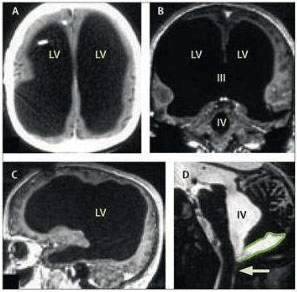

Hydrocéphalie

(Figure : vetopsy.fr d'après

Sciences magazine)